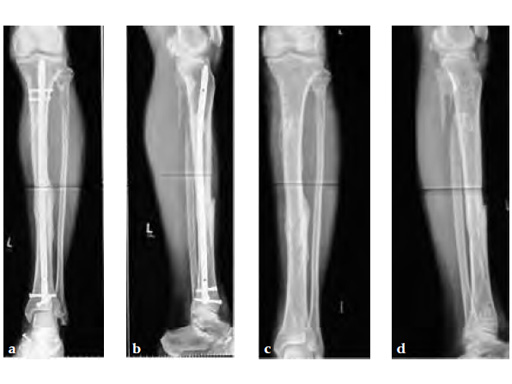

A 58-year-old male sustained a closed multifragmentary 42-C1 fracture in the distal tibia with compartment syndrome.

Case provided by Dankward Hntzsch, Tbingen, Germany

Primary treatment consisted of an external fixator and release of compartments.

Mobilization of the limb started with an applied external fixator.

Secondary treatment: insertion of an unreamed intramedullary nail with three ASLS screws inserted distally providing angular stability.

Partial weight bearing started on postoperative day 2 (with 2030kg). The weight was gradually increased over the following weeks. At 6 weeks, the patient was able to fully bear weight even though a high fibula fracture was present and no callus had yet formed. This suggests that angular stable interlocking of the nail markedly enhances stability. The patient was able to bear weight faster than planned and full weight bearing was possible with little pain.

Twelve-week follow-up shows callus formation, and the patient was able to fully bear weight without any pain.

The nail was removed 15 months postinjury as planned. There is good callus formation and proper healing of the tibia fracture.